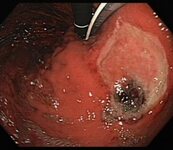

Ulcer in the mid-oesophagus with a visible vessel

From the collection of Douglas G. Adler, MD